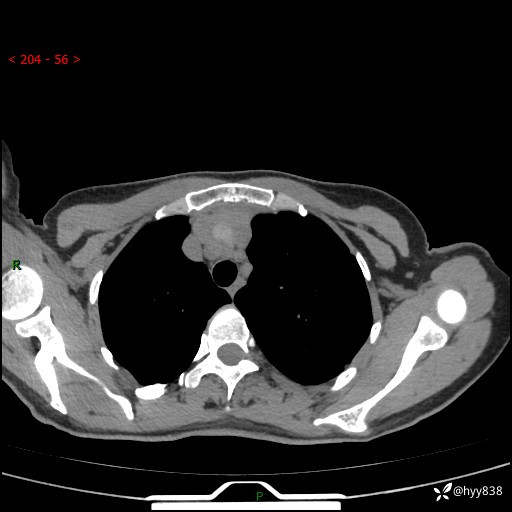

增强动脉期+静脉期